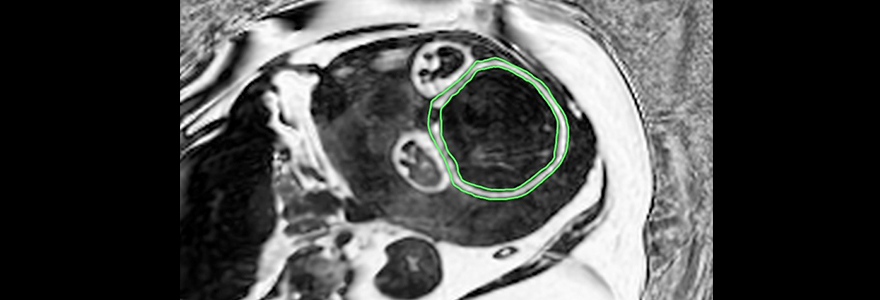

This increased efficiency allows time formerly used for spatial encoding to be invested instead in achieving order-of-magnitude increases in imaging speed, spatial resolution, or anatomical coverage of standard MRI images. Depending on the application this could allow 3D imaging of the whole heart in a single heart beat, 3D breast MRI at resolutions nearly as high as X-ray mammography or sub-millimeter resolution 3D MRI of the entire abdomen in a single breath hold. These gains in spatial encoding efficiency can also enable otherwise prohibitively time consuming examinations/techniques for crucial measurements of disease biomarkers.